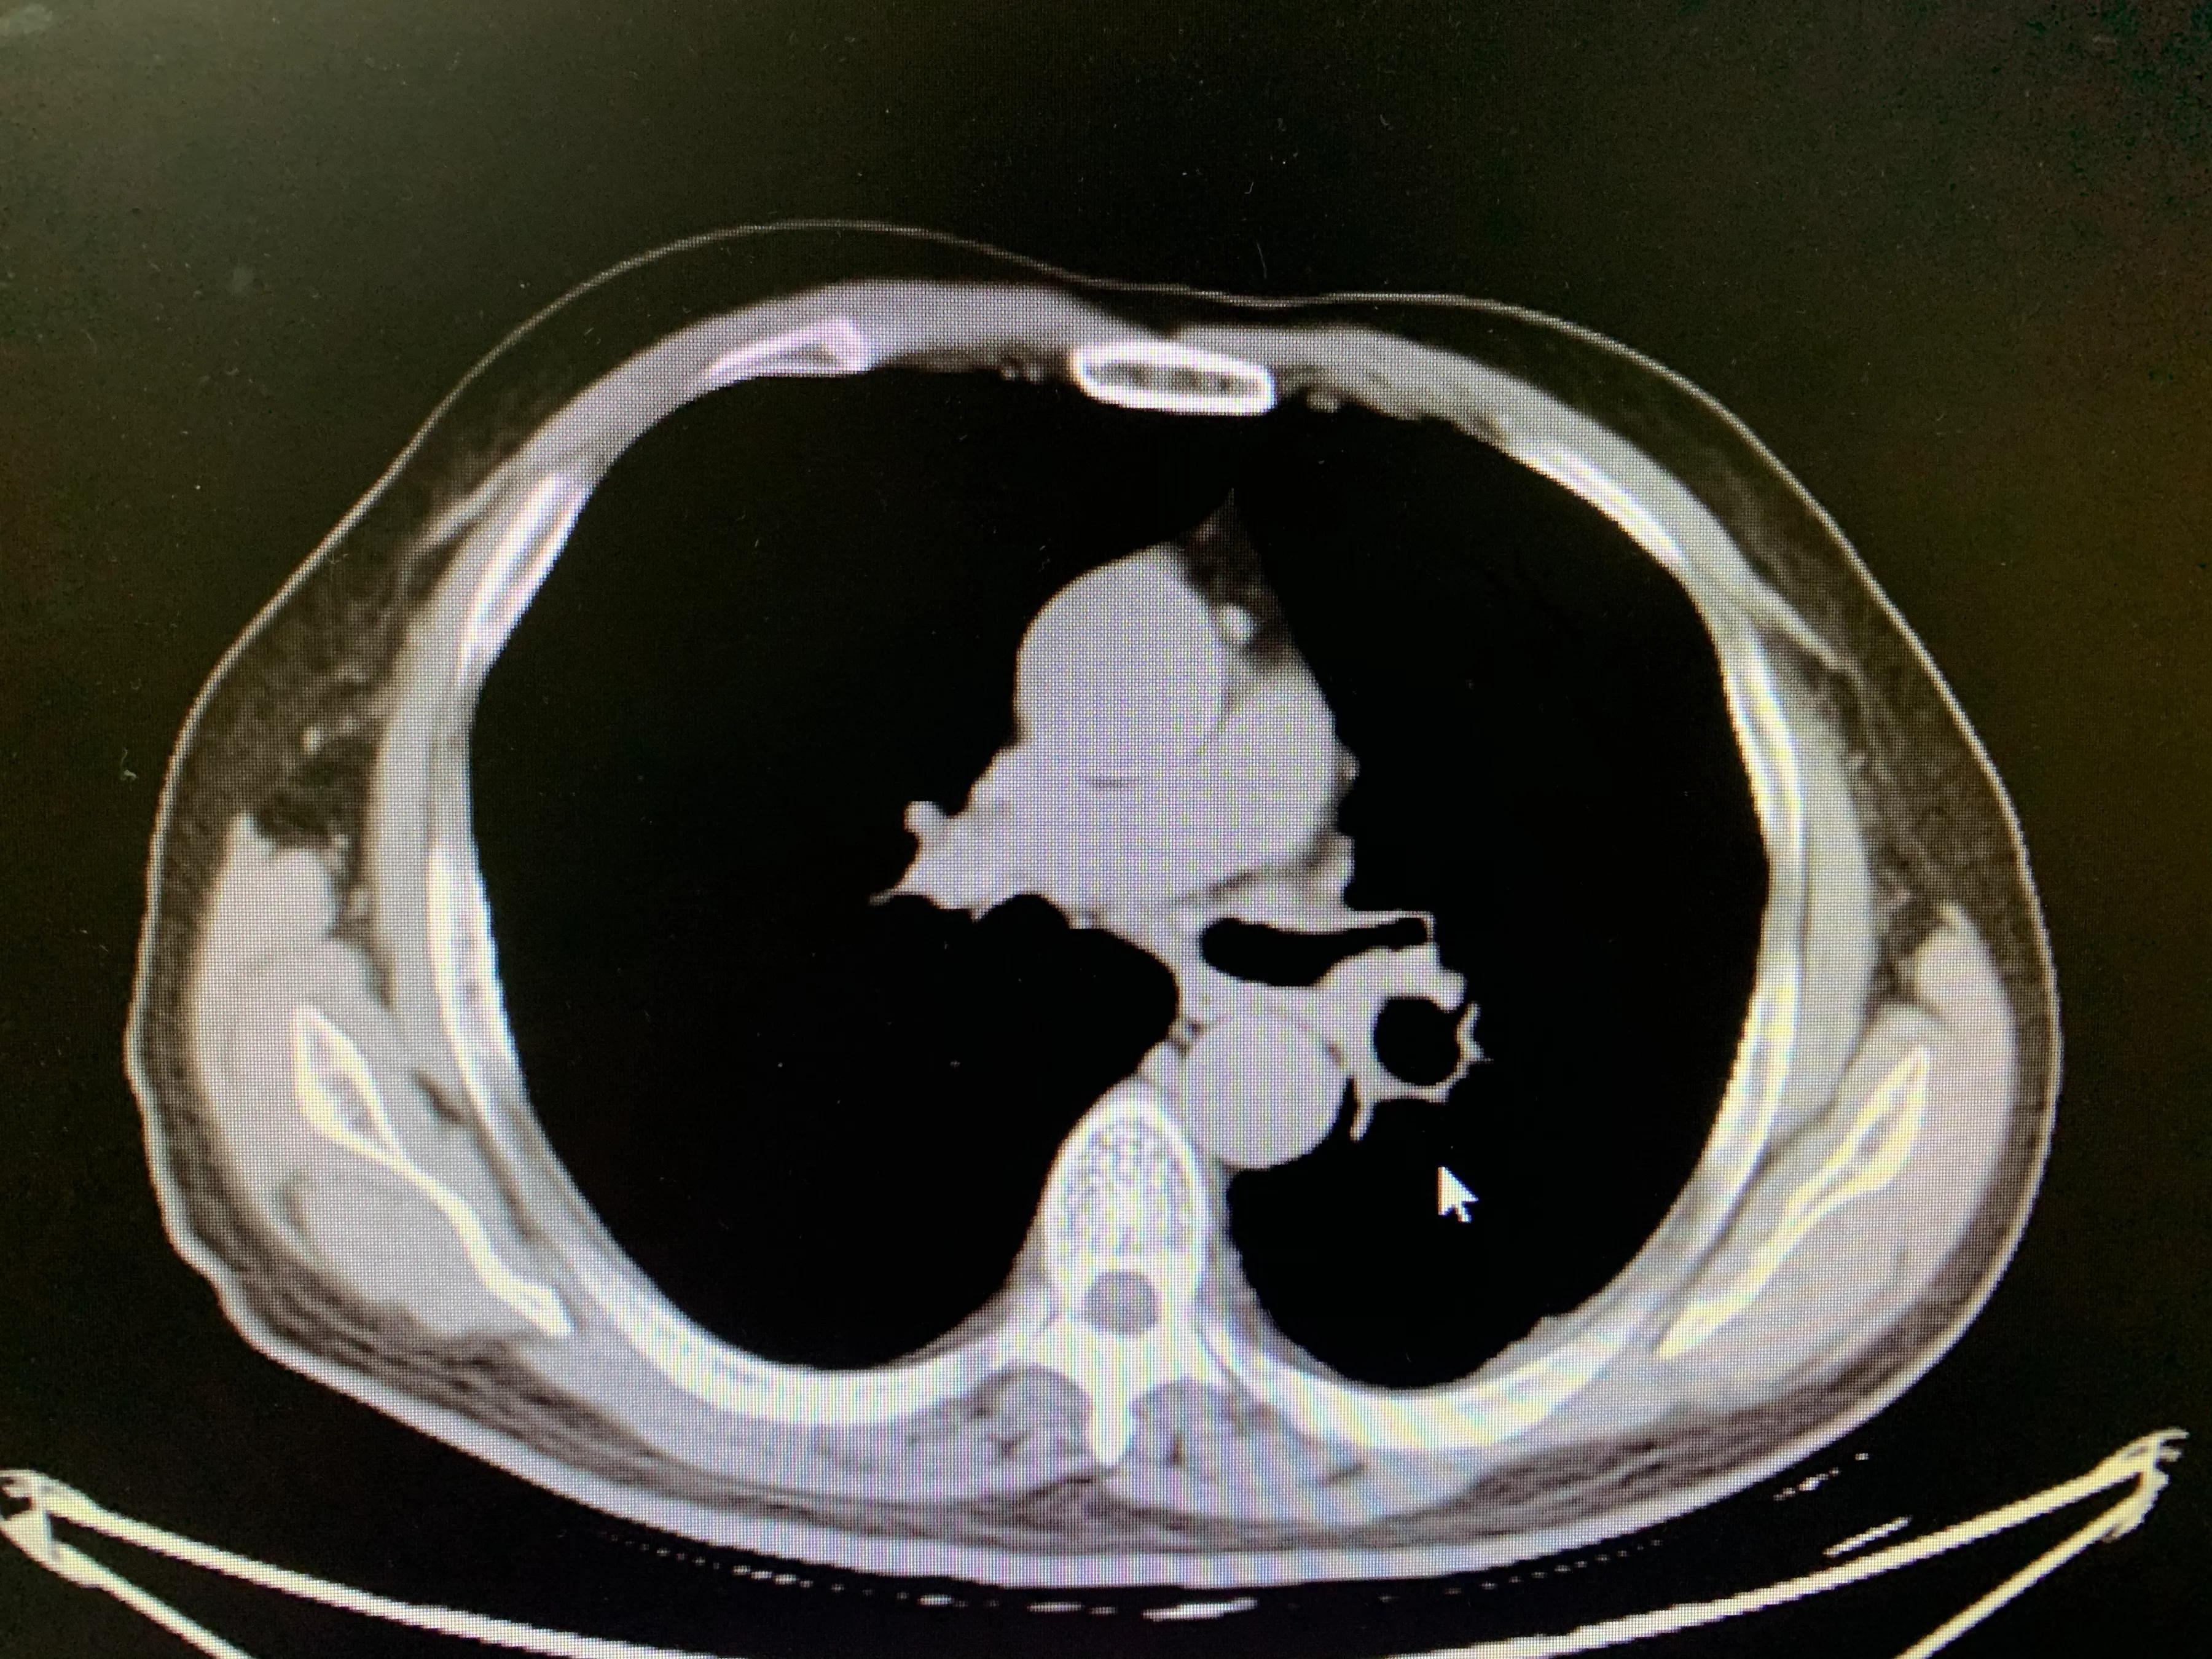

老年男性患者,左肺腺癌,化疗期间出现了咯血,术中可见左侧支气管动脉、左侧多支肋间动脉及左侧胸阔内动脉均参与肿瘤的血供,并可见以上动脉-肺动脉瘘,经肿瘤供血动脉灌注化疗药并且进行栓塞,术后未再出现咯血,一个月复查ct提示肿瘤较前明显减小,阻塞症状较前缓解。微创介入即经导管灌注化疗栓塞治疗肺肿瘤能够有效治疗肿瘤并且缓解肿瘤引起的一系列并发症,如咯血、阻塞性肺炎等,当然,肿瘤的治疗是综合治疗,需要多学科的共同参与。